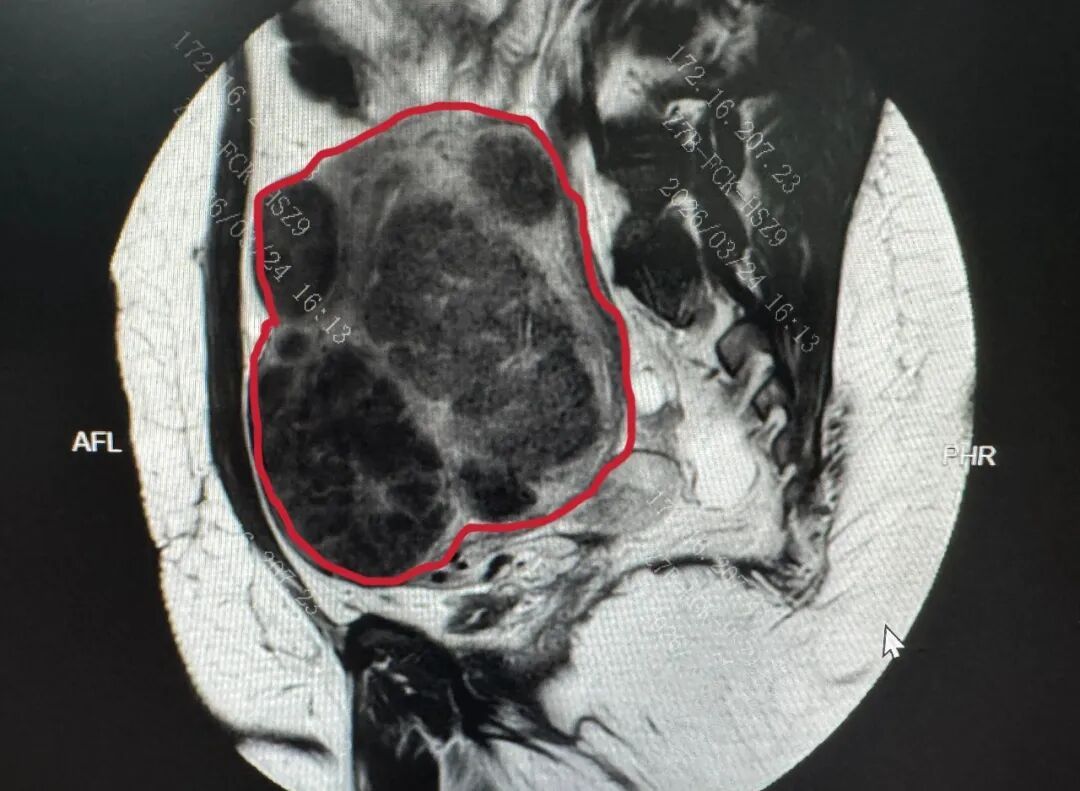

图示PUSH术前MRI子宫图像(红色线内区域为子宫)及子宫内弥漫存在的肌瘤影

更重要的是,安娜保宫、保生育的意愿极其强烈,手术不仅要剔净所有可见瘤体,还要最大限度保护正常子宫肌层,为未来生育留下足够空间。